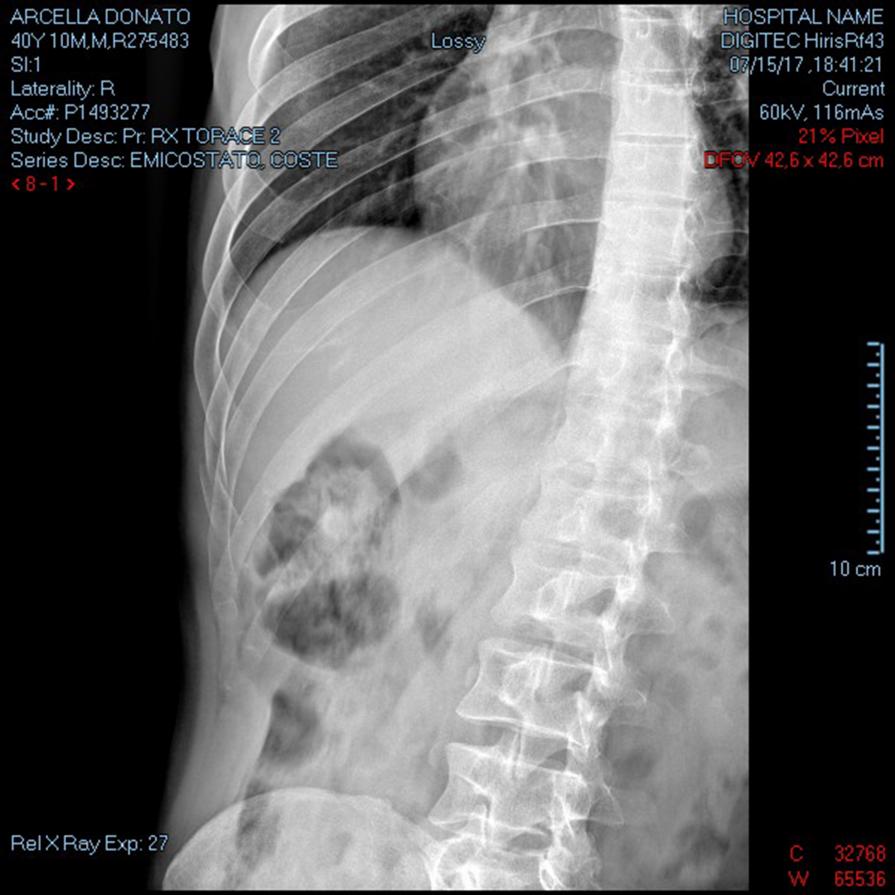

Emitorace DX ( autoritratto radiografia )

RX EMICOSTATO DX RX TORACE 2 PROIEZIONI RX TORACE ESPIRIUM Frattura lievemente scomposte all'arco posteriore della XI E XII costa e frattura scomposta all'arco anteriore dell'VIII costa dal lato destro, Frattura sostanzialmente composta all'arco medio-anteriore della X costa. Non evidenti falde pneumiche. Non apprezzabili versamenti pleurici né alterazioni parenchimali focali...